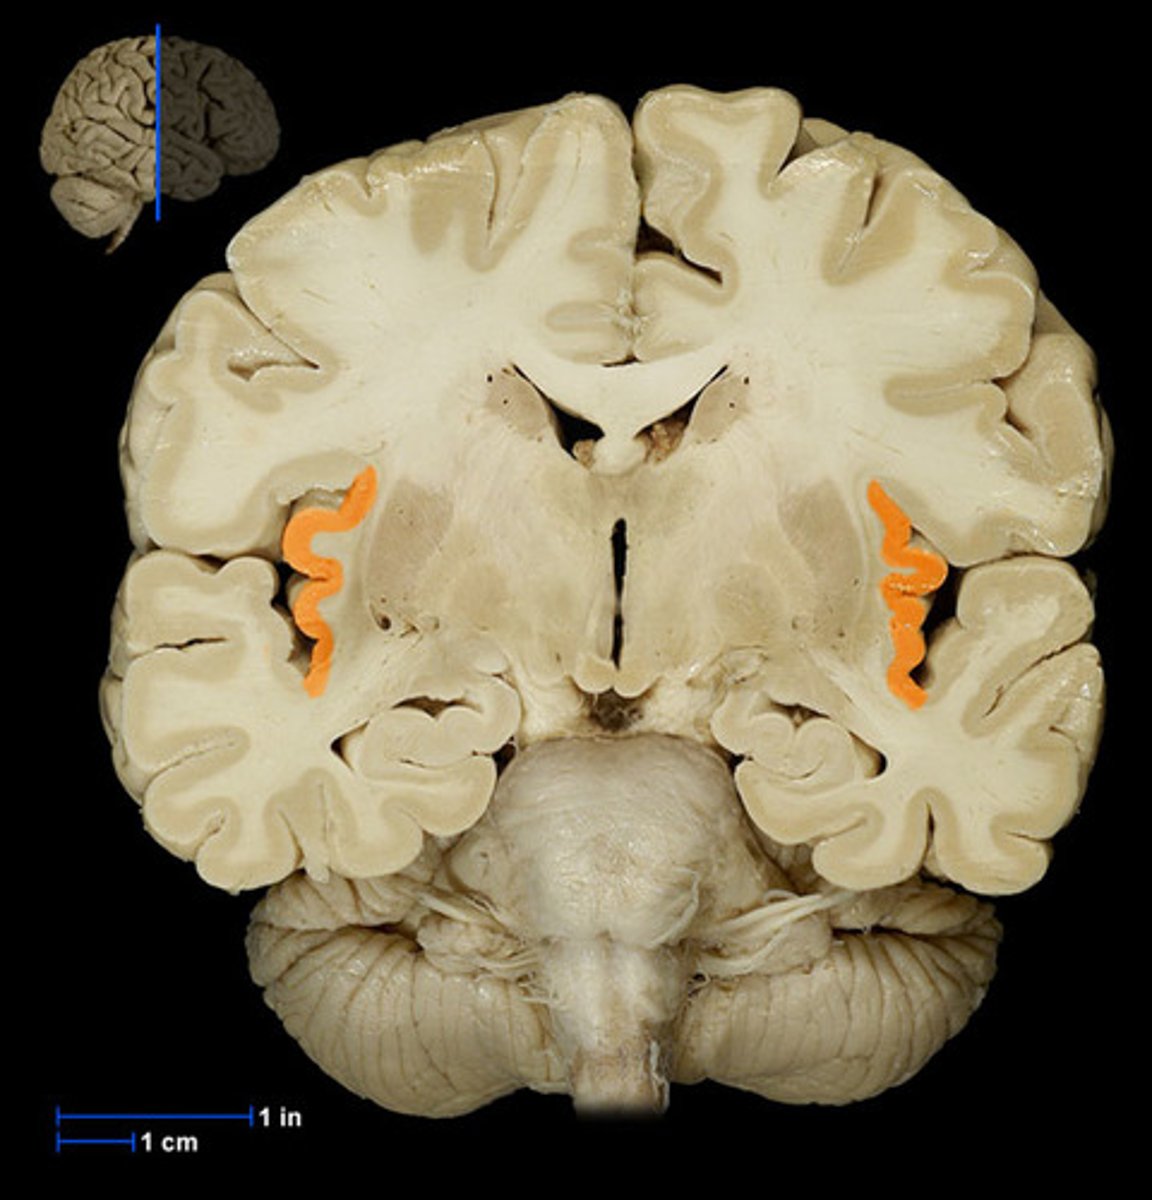

hippocampus

the region of the brain more caudal than the amygdala, snail appearance medial in the temporal lobe. Appears with the thalamus+third ventricle. plays a role in memory.

amygdala

rounded shape located medially in the temporal lobe. Appears with the hypothalamus, more rostral than the hippocampus. Plays a role in emotion.

One of the major nuclei that make up the basal ganglia. Head: Anterior to the thalamus, forming the lateral wall of the lateral ventricle.

Body: Extends posteriorly and laterally from the head, parallel to the thalamus.

Tail: Curves inferiorly and medially, lying above the temporal horn of the lateral ventricle.